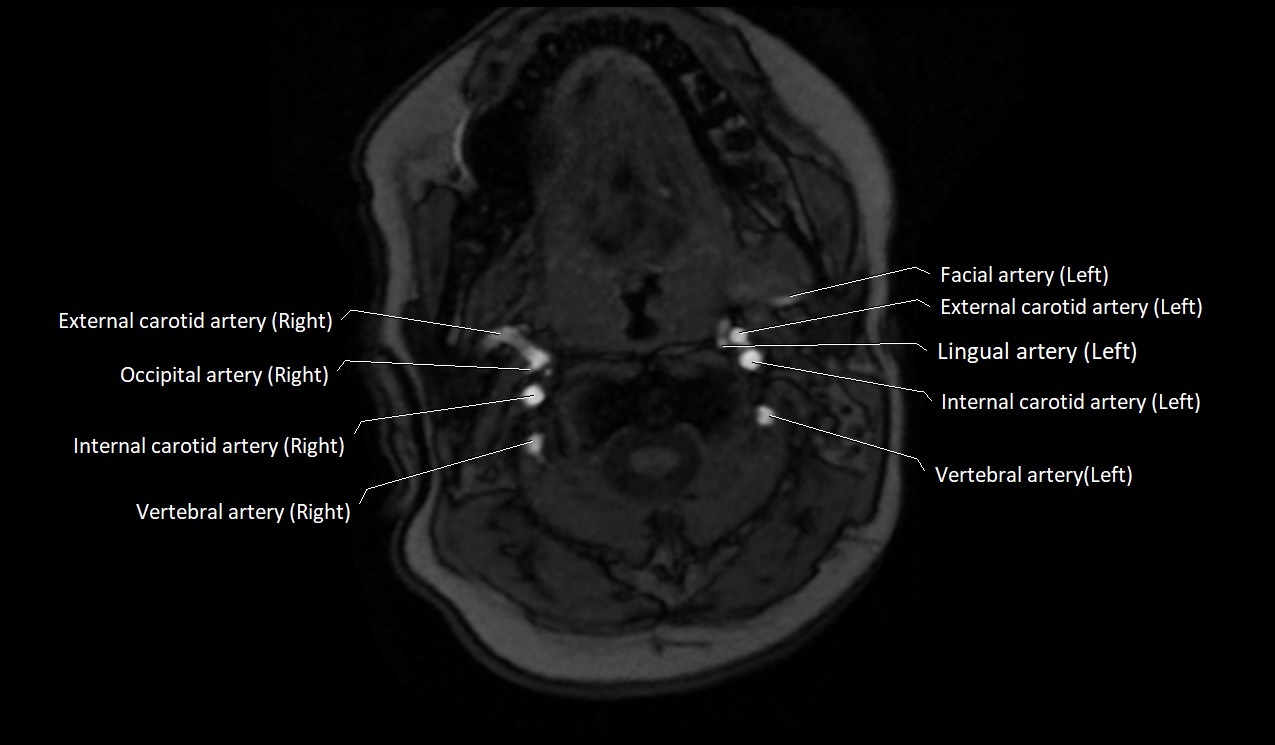

CT image

image